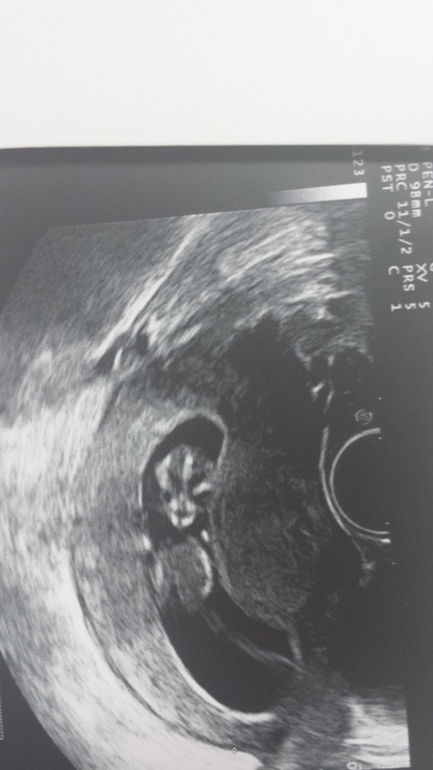

Первый наш скрининг

поздравляю со скринингом! Гематому лечи лежачим положением и не нервничай))Фотка смешная — на собачку похож)))Пол вам еще не предположили?

Тьфу! Очень милый инопланетянин:)

Он там как в космосе,космонавт,в невесомости,гыыы.пусть балдеет малыш.